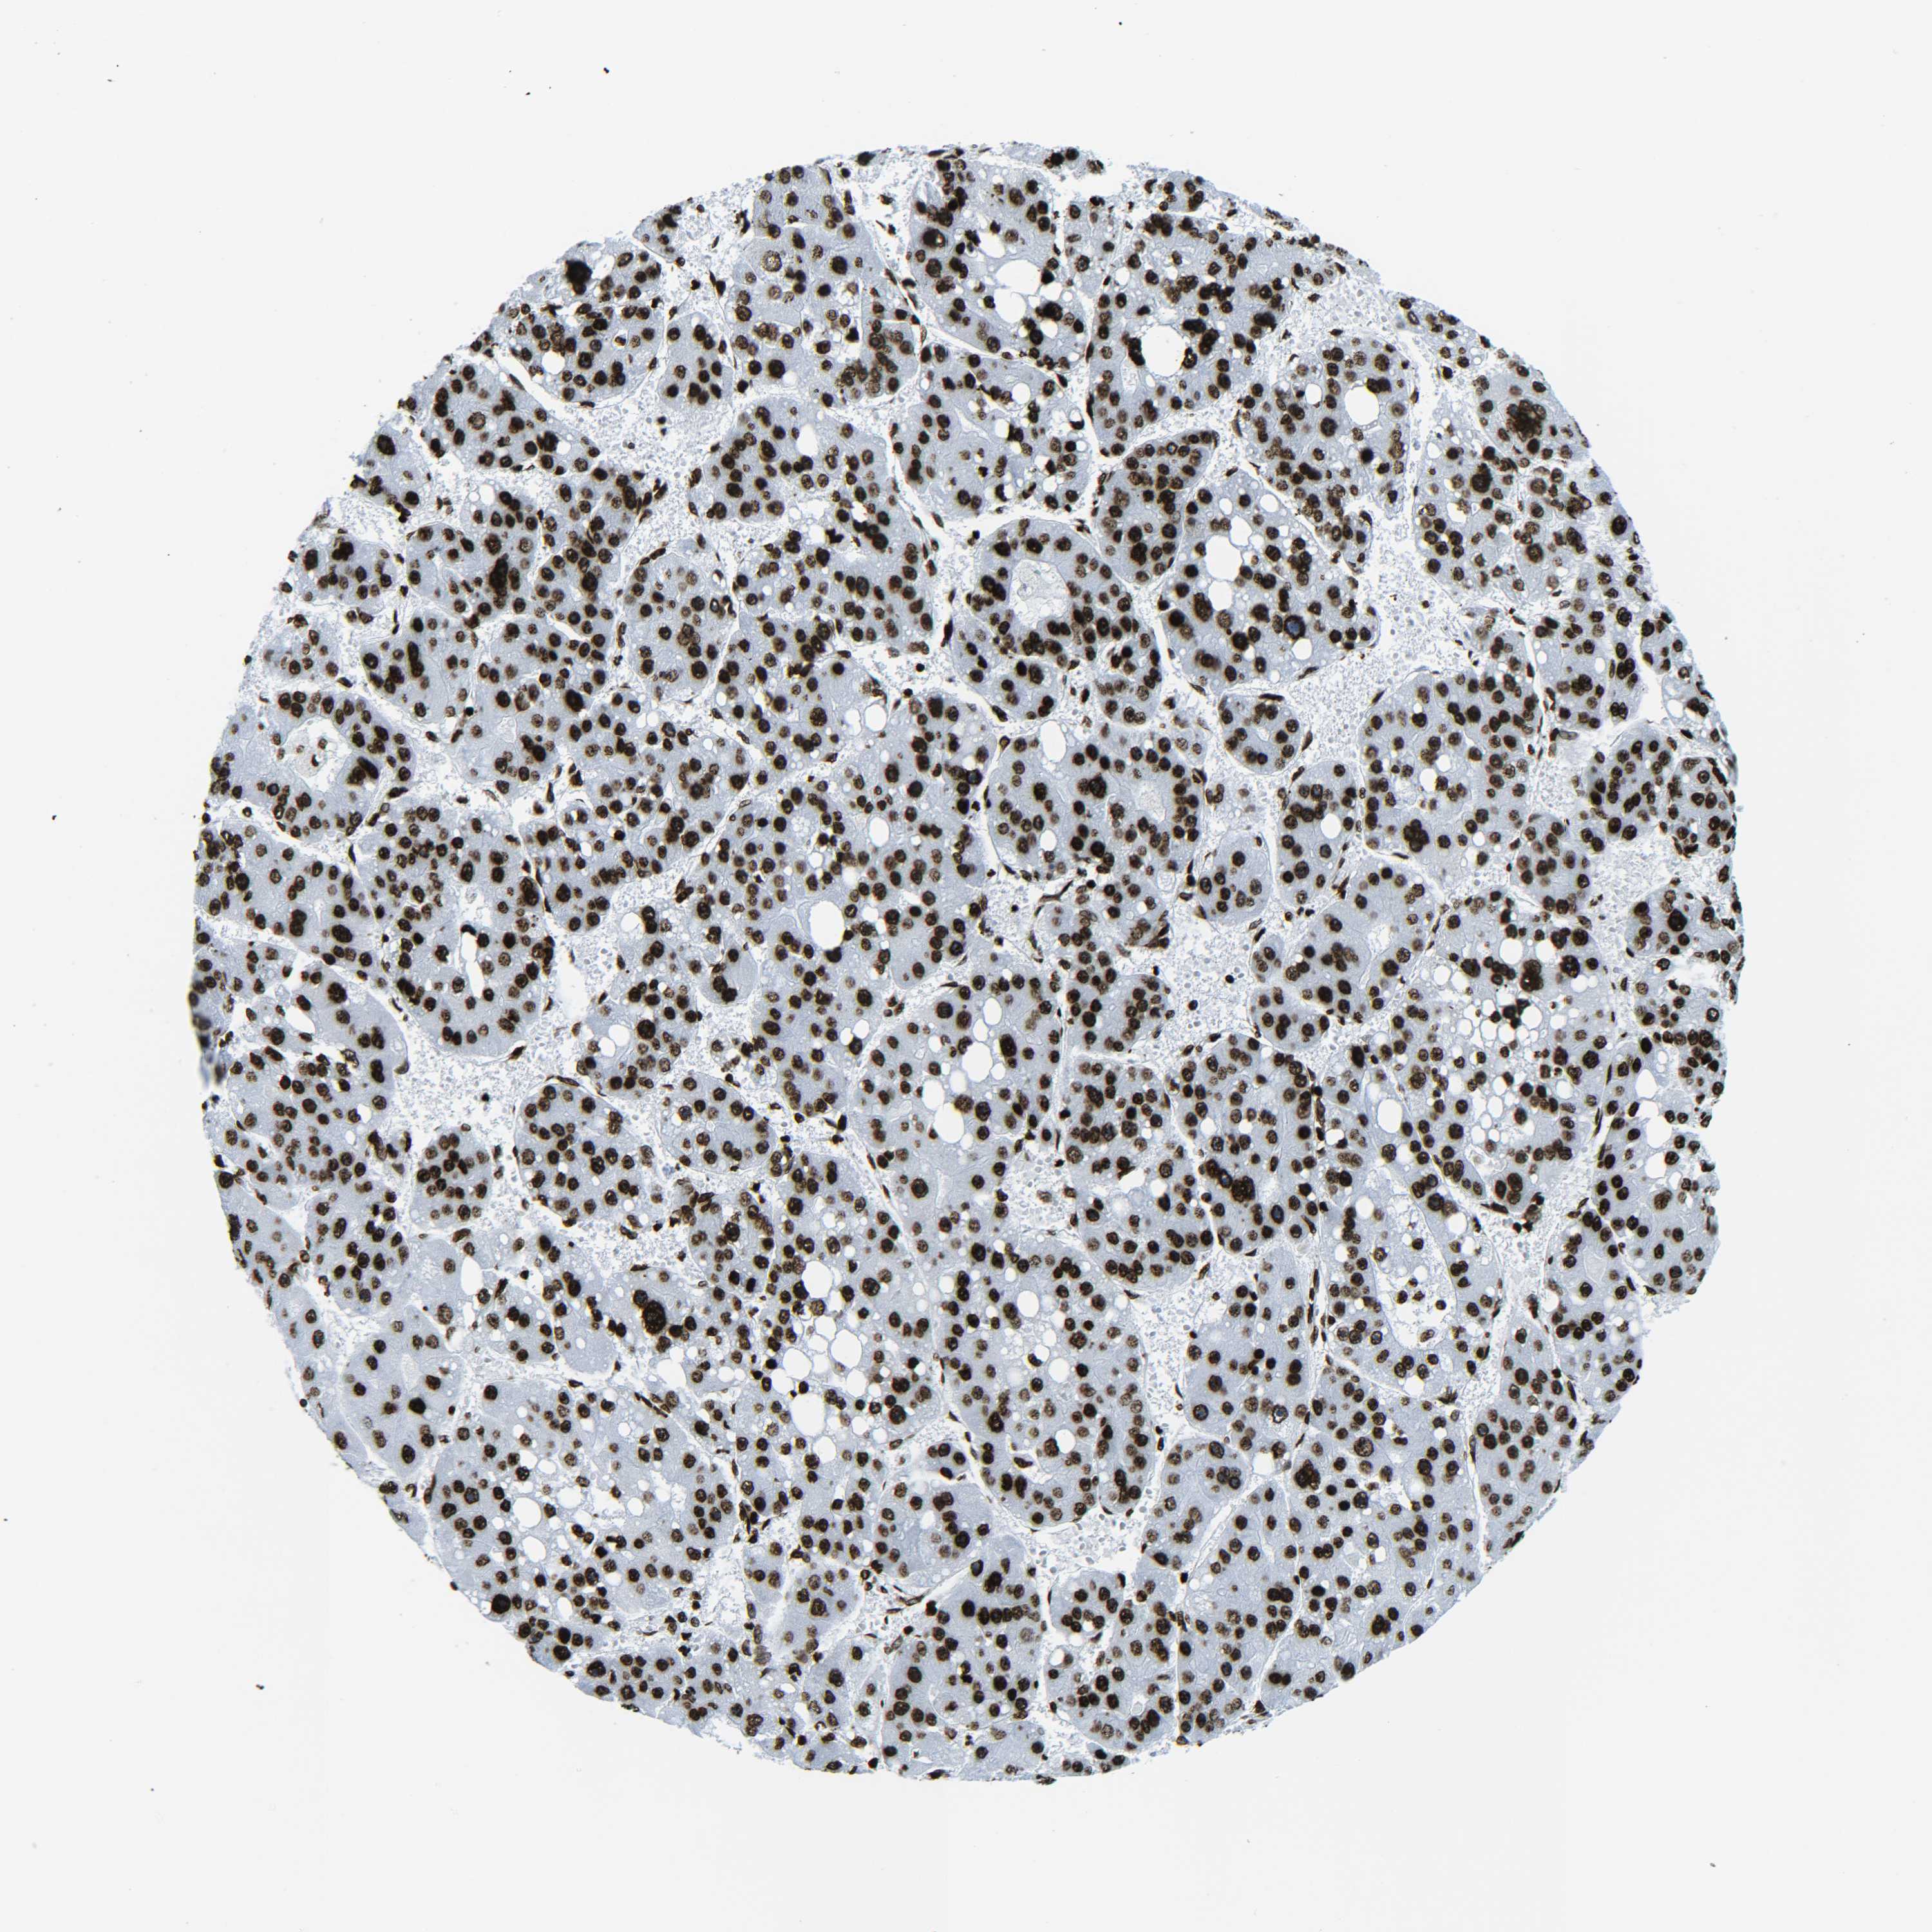

LIVER CANCER - Protein expressioni

A mouse-over function shows sample information and annotation data. Click on an image to view it in a full screen mode. Samples can be filtered based on level of antibody staining by selecting one or several of the following categories: high, medium, low and not detected. The assay and annotation is described here.

Note that samples used for immunohistochemistry by the Human Protein Atlas do not correspond to samples in the TCGA dataset.

Antibody stainingi

Antibody staining in the annotated cell types in the current human tissue is reported as not detected, low, medium, or high, based on conventional immunohistochemistry profiling in selected tissues. This score is based on the combination of the staining intensity and fraction of stained cells.

Each image is clickable and will lead to virtual microscopy that enables deeper exploration of all samples and also displays staining intensity scores, fraction scores and subcellular localization as well as patient and tissue information for each sample.

Antibody HPA041189

Antibody HPA051647

Antibody CAB012264

Staining

High

Medium

Low

Not detected

Intensity

Strong

Moderate

Weak

Negative

Quantity

>75%

75%-25%

<25%

None

Location

Nuclear

Cytoplasmic/membranous

Cytoplasmic/membranous,nuclear